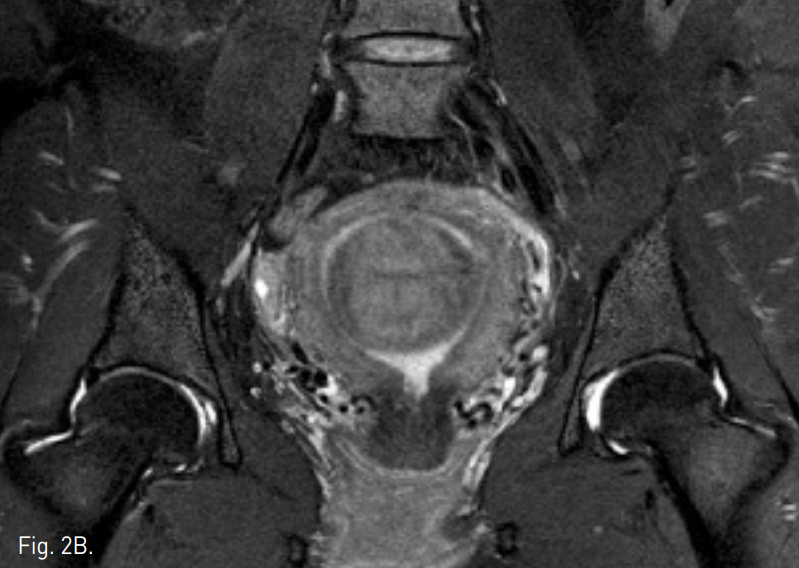

Fig. 3

A. Pelvic angiography shows bilateral hypertrophied uterine arteries.

B. Pelvic angiography shows a hypervascular tumor staining of the uterine fibroid.

C, D. After uterine ar tery embolization, hypertrophied uterine artery could not be seen.